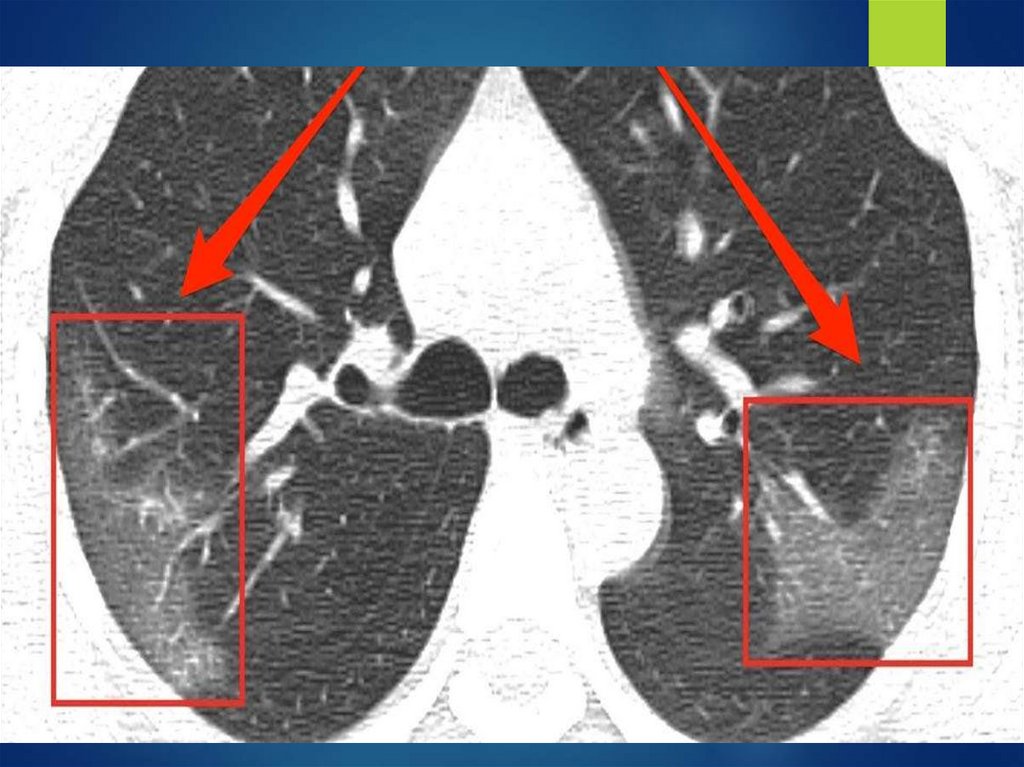

ОБОБЩЕННОЕ ПОНЯТИЕ ЛЕГОЧНОЙ

ДИССЕМИНАЦИИ